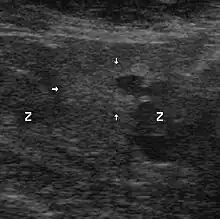

Le diagnostic est obtenu par des biopsies prostatiques multiples, réalisées de manière échoguidée et par voie transrectale. Elle permet également de réaliser le score de Gleason, de grande valeur pronostique.

Échographie avec biopsies transrectales

Il n'existe actuellement aucun examen d'imagerie de pratique courante susceptible de détecter seul un foyer d'adénocarcinome prostatique avec une sensibilité et une spécificité satisfaisantes.

Contrairement à une idée encore largement répandue, et bien que cet examen soit ainsi encore souvent prescrit, l'échographie endorectale, seule, n'a pas d'utilité pour le diagnostic positif du cancer de la prostate, au regard du désagrément qu'elle est susceptible d'occasionner. Elle prend, en revanche, tout son intérêt lorsqu'elle sert à guider des biopsies prostatiques. Les autres modalités d'imagerie (scanner, IRM) ont un intérêt dans le bilan d'extension.

Technique

Une sonde d'échographie endorectale munie d'un guide d'aiguille est introduite dans le rectum. Les biopsies sont effectuées avec des aiguilles munies d'un mandrin encoché. Le mandrin pénètre le premier. L'aiguille vient le recouvrir, pour trancher et emprisonner ainsi le fragment de prostate situé dans l'encoche. Les mouvements du mandrin et de l'aiguille sont automatisés par un système de ressorts et le prélèvement est effectué en quelques centièmes de seconde. L'écran de l'échographe, muni d'un repère représentant le trajet de l'aiguille, permet, ainsi, des tirs biopsiques très précis.